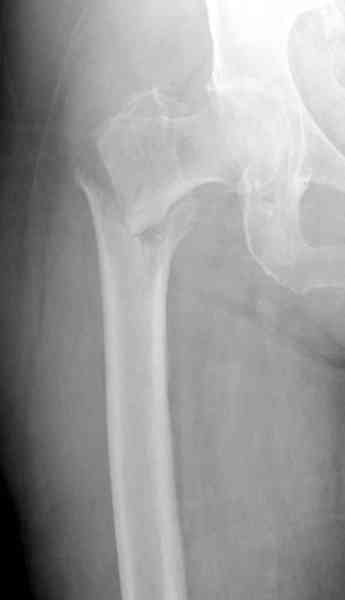

Александр, поздравляю от души, отличная работа, вообще-то и у меня тоже были опасения по поводу латеральной стенки. Идеальное показаниt к применению импланта закрытым методом при таких переломах, когда болт замыкается в штифте, конструкции придается угловая жесткость, примерно как в Blade Plate.

Здесь сканнированные снимки импланта и операционные снимки больной.